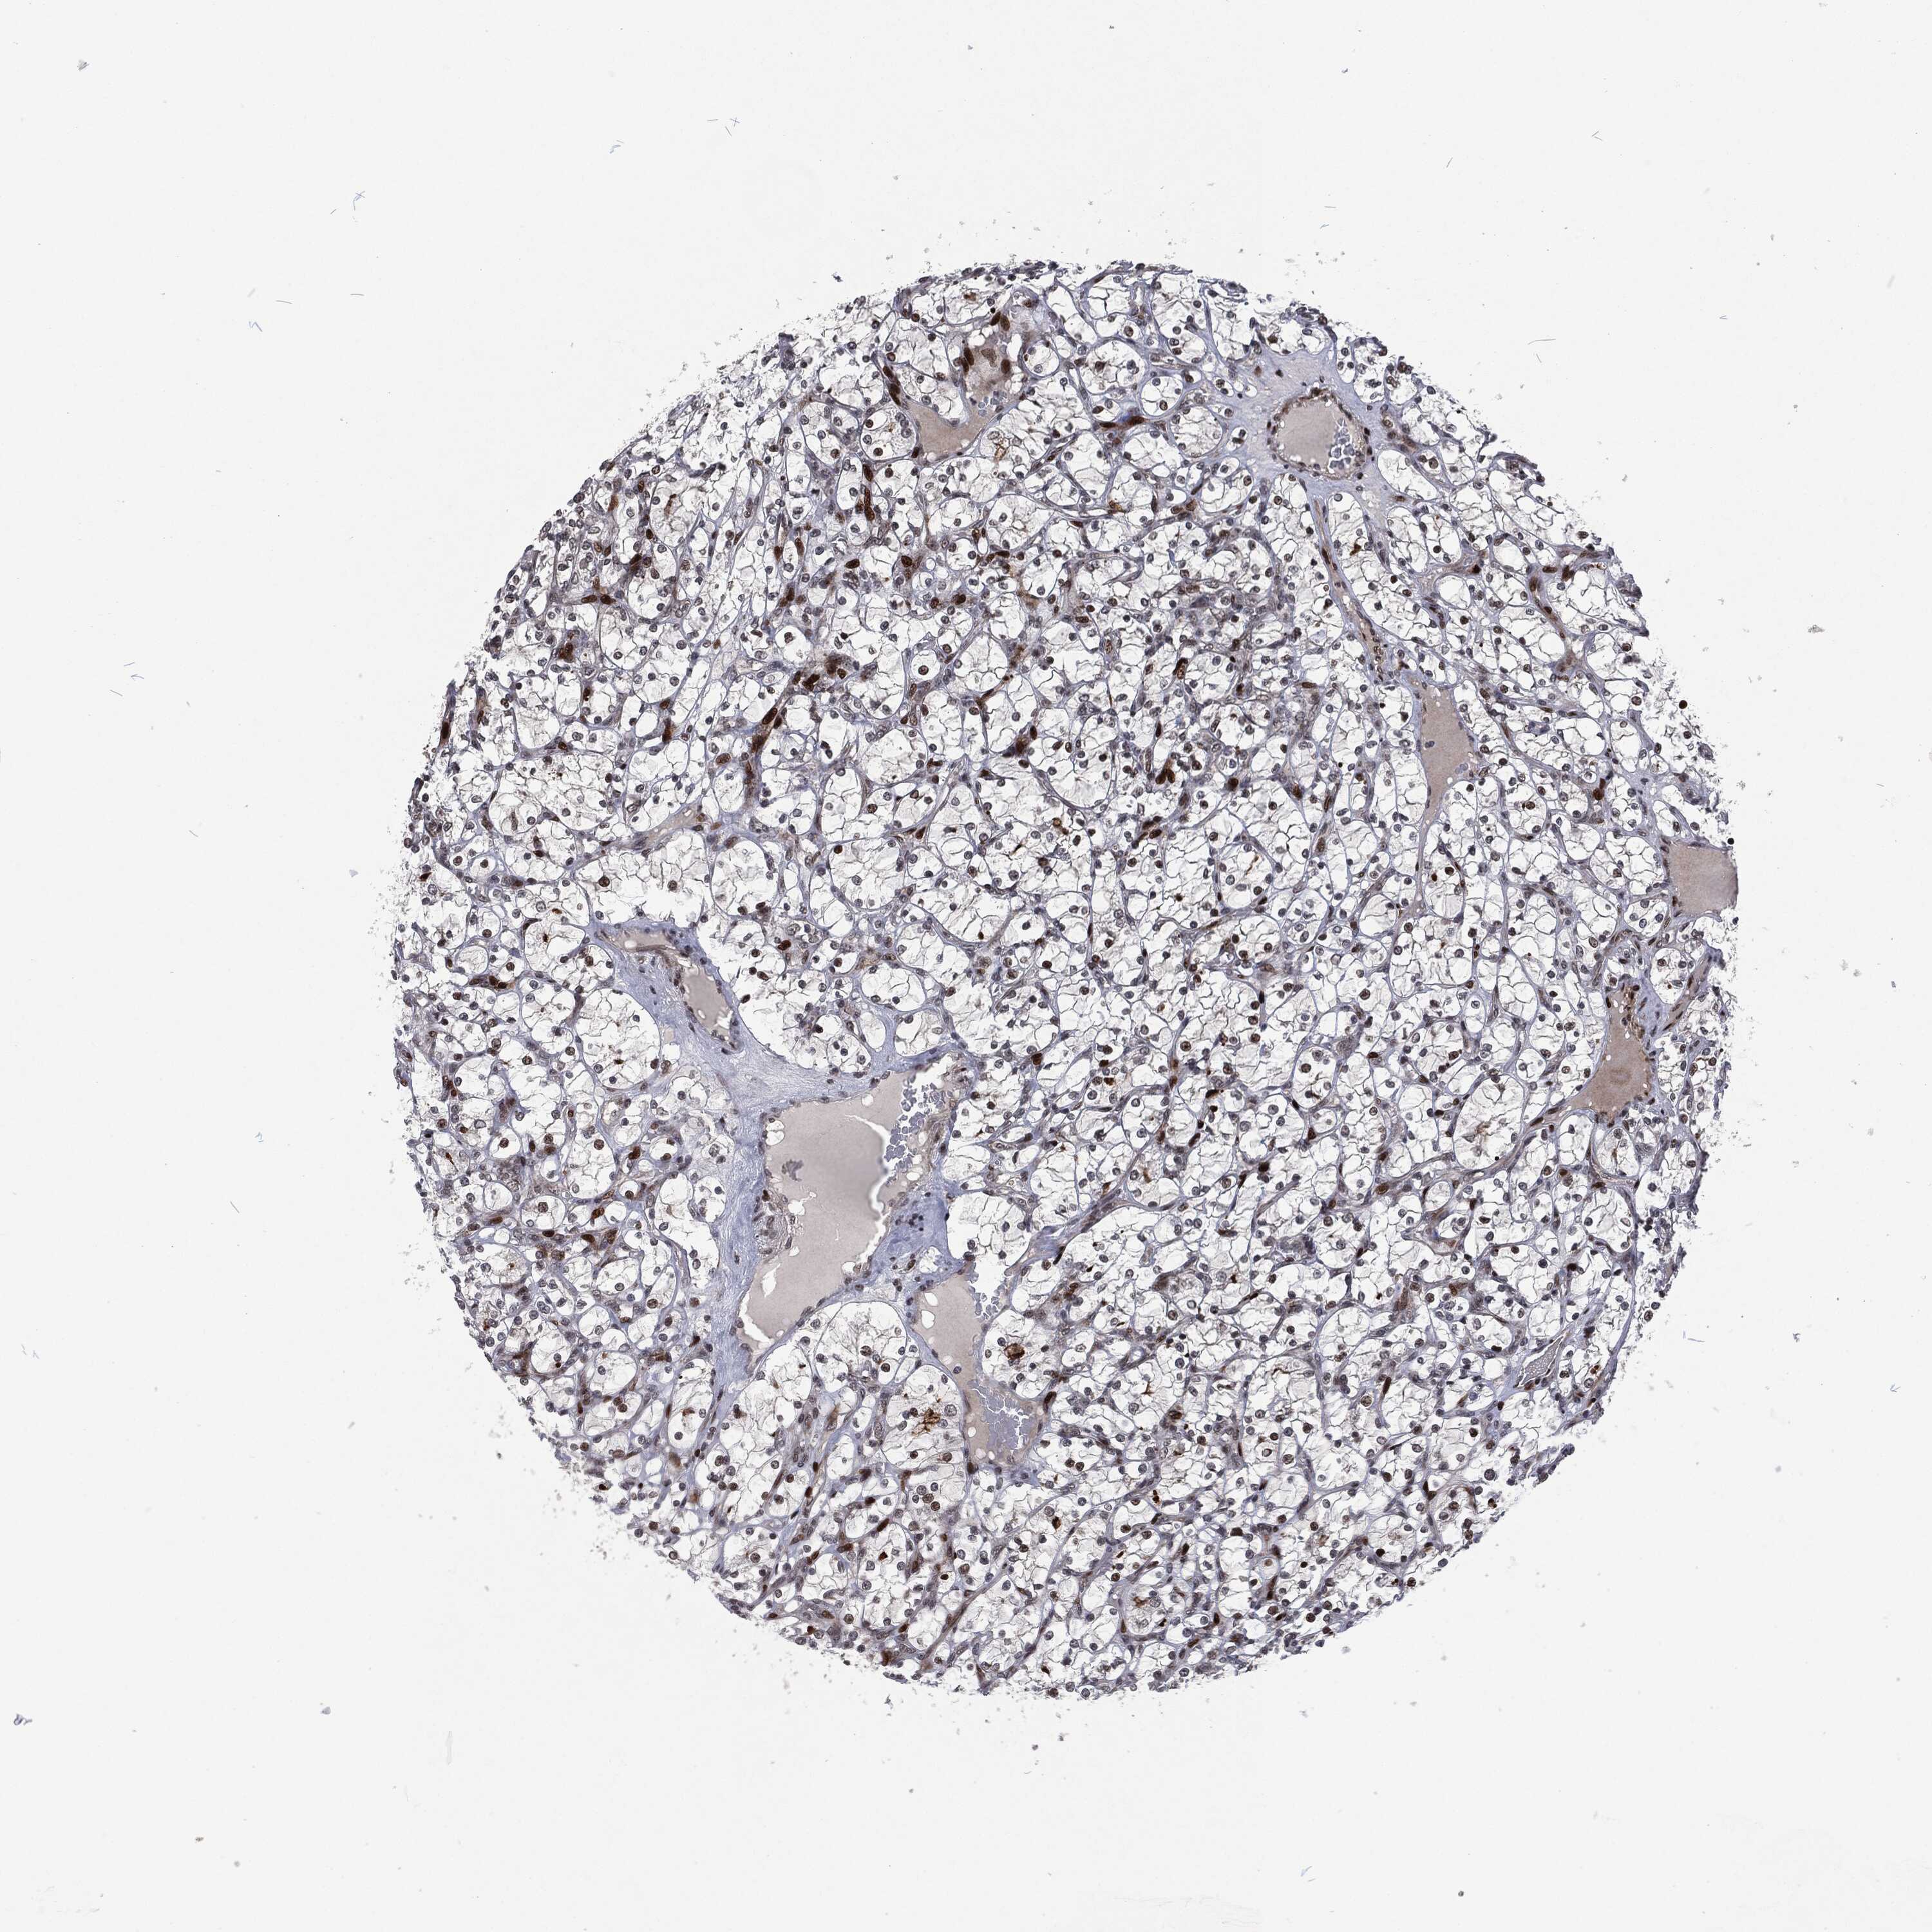

KIDNEY RENAL CLEAR CELL CARCINOMA (VALIDATION) - Interactive survival scatter ploti

The Survival Scatter plot shows the clinical status (i.e. dead or alive) for all individuals in the patient cohort, based on the same data that underlies the corresponding Kaplan-Meier plots. Patients that are alive at last time for follow-up are shown in blue and patients who have died during the study are shown in red.

The x-axis shows the expression levels (FPKM) of the investigated gene in the tumor tissue at the time of diagnosis. The y-axis shows the follow-up time after diagnosis (years). Both axes are complimented with kernel density curves demonstrating the data density over the axes. The top density plot shows the expression levels (FPKM) distribution among dead (red) and alive patients (blue). The right density plot shows the data density of the survived years of dead patients with high and low expression levels respectively, stratified using the cutoff indicated by the vertical dashed line through the Survival Scatter plot. This cutoff is automatically defined based on the FPKM cutoff that minimizes the p-score. The cutoff can be changed by dragging the vertical line or by entering a cutoff value in the square labeled "Current cut-off".

Under the Survival Scatter plot the p-score landscape (black curve; left axis) is shown together with dead median separation (red curve; right axis). Dead median separation is the difference in median mRNA expression between patients who have died with high and low expression, respectively. It is calculated as follows: median FPKM expression of dead patients with high expression - median FPKM expression of dead patients with low expression. This is intended to aid the user in visually exploring custom cutoffs and the associated p-scores and dead median separation.

Individual patient data is displayed and can be filtered by clicking on one or more of the category buttons on the top of the page. Categories describing expression level and patient information include: high, low, alive, dead, female, male and tumor stages. The scale of the x-axis can be toggled between linear and log-scale by clicking on the "x log" button. Mouse-over function shows TCGA ID, patient information and mRNA expression (FPKM) for each patient.

& Survival analysisi

Kaplan-Meier plots summarize results from analysis of correlation between mRNA expression level and patient survival. Patients were divided based on level of expression into one of the two groups "low" (under cut off) or "high" (over cut off). X-axis shows time for survival (years) and y-axis shows the probability of survival, where 1.0 corresponds to 100 percent.

EGFR is not prognostic in Kidney Renal Clear Cell Carcinoma (validation)

: 44.55

Average pTPM 89.3

Number of samples 100